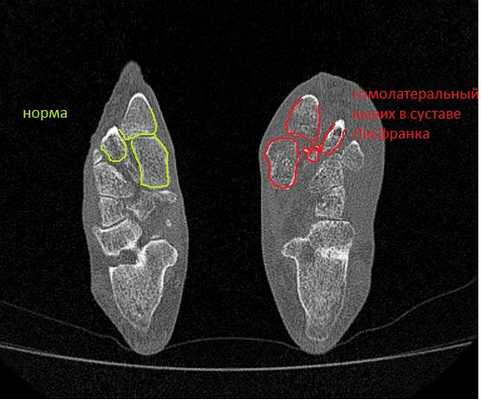

В сложных с диагностической точки зрения случаях целесообразно использование КТ и МРТ.

Лучше - сделать КТ исследование, где в сравнении со здоровой стороной будет очень хорошо видно повреждение.